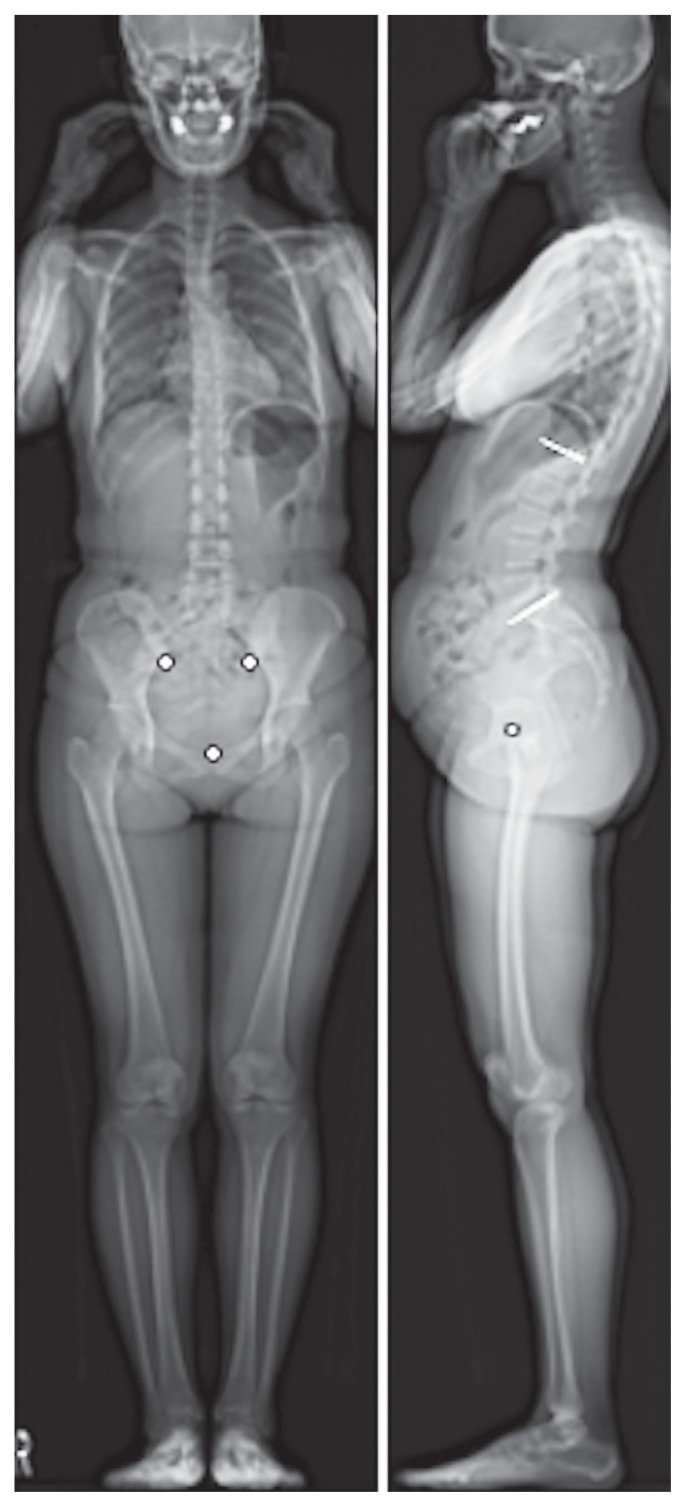

Purpose: To determine the effectiveness of the pelvic ring ratio as an indicator for assessing pelvic tilt (PT) from the frontal view and explore its correlation with various whole-body sagittal alignment (WBSA) parameters using EOS imaging technology.

Overview of literature: Traditional indicators of PT often rely on sagittal plane measurements, which can be challenging in cases of pelvic rotation or obesity. A new indicator such as the pelvic ring ratio could address these challenges and aid in the comprehensive assessment of pelvic alignment.

Methods: In total, 104 healthy participants (28 men, 76 women; mean age, 52.8±12.3 years) with no spinal disorders were recruited. Whole-body radiography using the EOS imaging system was performed to obtain sagittal and coronal parameters, including the pelvic ring ratio. Intra- and interobserver variability were assessed using intraclass correlation coefficients (ICCs) based on measurements by three spine surgery specialists. Correlation analyses among the pelvic ring ratio, age, body mass index, and WBSA parameters were conducted, and a multiple linear regression model was developed to predict PT.

Results: The mean pelvic ring ratio was 53.3%±11.5%. The intra- and interobserver ICCs were 0.89 and 0.87, respectively, indicating good reliability. The pelvic ring ratio was negatively correlated with age (r =-0.387, p <0.05) and PT (r =-0.598, p <0.05). The regression model revealed that the pelvic ring ratio and sex significantly predicted PT (p <0.05). Women had higher pelvic ring ratio (55.0%±11.3%) than men (48.6%±10.8%).

Conclusions: The pelvic ring ratio is a reliable and valuable indicator for PT assessment from the frontal view. It exhibits significant correlations with age and certain WBSA parameters, showing potential to improving the diagnostic accuracy and treatment planning for patients with spinal and hip disorders.